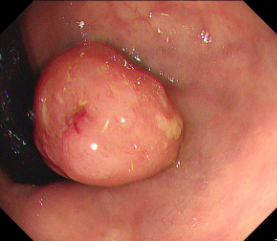

Polyps are early cancer indicators, so assessing occurrences of polyps and their removal is critical. They are observed through a colonoscopy screening procedure that generates a stream of video frames. Segmenting polyps in their natural video screening procedure has several challenges, such as the co-existence of imaging artefacts, motion blur, and floating debris. Most existing polyp segmentation algorithms are developed on curated still image datasets that do not represent real-world colonoscopy. Their performance often degrades on video data. We propose a video polyp segmentation method that performs self-supervised learning as an auxiliary task and a spatial-temporal self-attention mechanism for improved representation learning. Our end-to-end configuration and joint optimisation of losses enable the network to learn more discriminative contextual features in videos. Our experimental results demonstrate an improvement with respect to several state-of-the-art (SOTA) methods. Our ablation study also confirms that the choice of the proposed joint end-to-end training improves network accuracy by over 3% and nearly 10% on both the Dice similarity coefficient and intersection-over-union compared to the recently proposed method PNS+ and Polyp-PVT, respectively. Results on previously unseen video data indicate that the proposed method generalises.